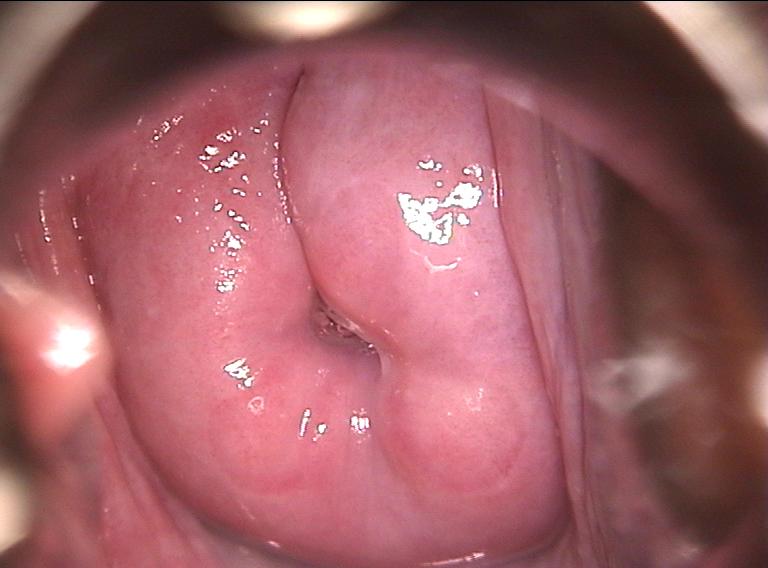

Colposcopy is a gynecological procedure that illuminates and magnifies the vulva, vaginal walls, and uterine cervix (mouth of the uterus) in order to detect and examine abnormalities of these structures.

A colposcope is a microscope that resembles a pair of binoculars. The instrument has a range of magnification lenses. It also has color filters that allow the physician to detect tiny abnormal blood vessels on the cervix. The colposcope is used to examine the vaginal walls and cervix through the vaginal opening.

The examiner wants to get a good look at the squamocolumnar junction, which is the area of the cervix that gives rise to most cases of cervical cancer. The term squamocolumnar junction refers to the border between the two different types of cells (squamous cells and columnar cells) that normally form the lining of the endocervical canal. (This canal connects the cervix with the main part of the uterus.) Most cases of cervical cancer originate from the squamous cells and, therefore, are referred to as squamous cell cervical cancer.